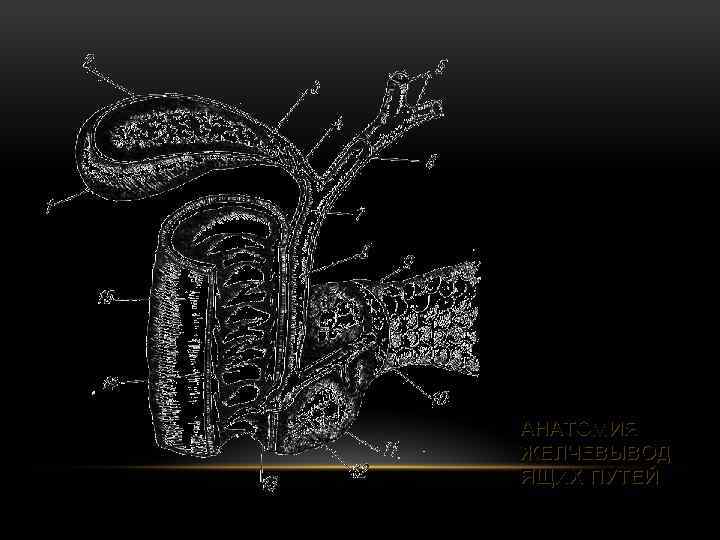

АНАТОМИЯ ЖЕЛЧЕВЫВОД ЯЩИХ ПУТЕЙ

АНАТОМИЯ ЖЕЛЧЕВЫВОД ЯЩИХ ПУТЕЙ